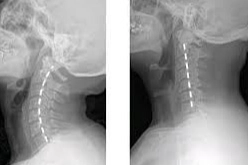

Boyun düzleşmesi, genellikle boyun omurlarının doğal eğrisinin kaybolduğu bir durumu ifade eder. Bu duruma tıp dilinde "boyun düzleşmesi" veya "servikal lordoz kaybı" denir ve çeşitli nedenlerle ortaya çıkabilir. İşte boyun düzleşmesinin başlıca nedenleri:

Disk Dejenerasyonu: Yaşlanma süreciyle birlikte, boyun omurlarındaki diskler su kaybeder ve elastikiyetlerini kaybeder, bu da düzleşmeye neden olabilir.5. Doğumsal ve Genetik Faktörler